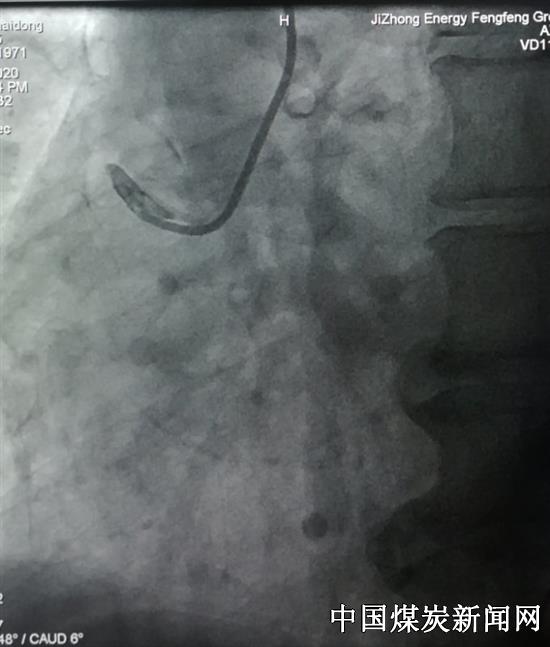

47岁的王先生因胸闷、胸痛、大汗夜晚就诊急诊科,心电检查:急性下壁、后壁、右室心肌梗死。心内一科主任王溥、副主任李玲及刘香格护士长接到急救通知后以最快的速度赶到,护送病人到介入导管室进行急诊冠脉微创介入术,冠状动脉造影示:右冠闭塞,患者阻塞血管极其粗大,但因血管极度迂曲,固定狭窄重,指引导管不给力,导丝无法通过,介入手术难度非常大。

王溥和李玲商议决定先给患者经指引导管给药进行冠脉内溶栓降低了出血风险。血管出现部分再通后,导丝终于通过了闭塞病变,到达了血管远段,成功地为病人在迂曲且狭窄最重部位植入了支架。这名患者右冠状动脉非常粗,梗死面积极大,如果不及时开通闭塞血管,患者死亡危险高,还会导致残疾。